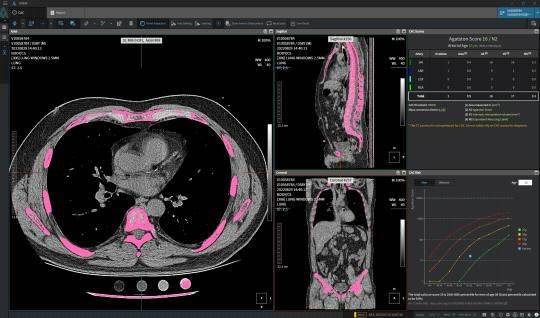

| ▲ ㈜코어라인소프트의 심폐질환 진단을 위한 AI 기반 소프트웨어의 해외 임상 검증 및 FDA 인증 사례 |

| ⓒ 한국보건산업진흥원 제공 |

국제협력연구에서 ▲흉부 CT영상 활용 폐암 조기 진단 인공지능 소프트웨어 ▲소화기관 조기 암질환 대상 복부 최소침습 수술로봇 ▲혈중 내 바이오마커 활용 대장암 선별 체외진단 의료기기 ▲갑상선 기능이상 및 안병증 소프트웨어 의료기기 등 4건의 기술과 해외임상지원에서 ▲ 흉부 CT영상 활용 심폐질환 진단 인공지능 소프트웨어 1건이 그것이다.